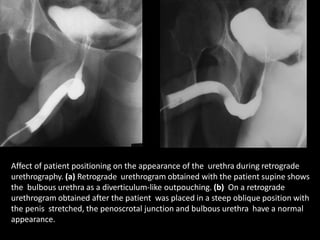

Affect of patient positioning on the appearance of the urethra during retrograde

urethrography. (a) Retrograde urethrogram obtained with the patient supine shows

the bulbous urethra as a diverticulum-like outpouching. (b) On a retrograde

urethrogram obtained after the patient was placed in a steep oblique position with

the penis stretched, the penoscrotal junction and bulbous urethra have a normal

appearance.